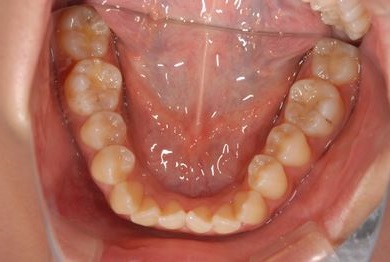

治療前

• 治療前